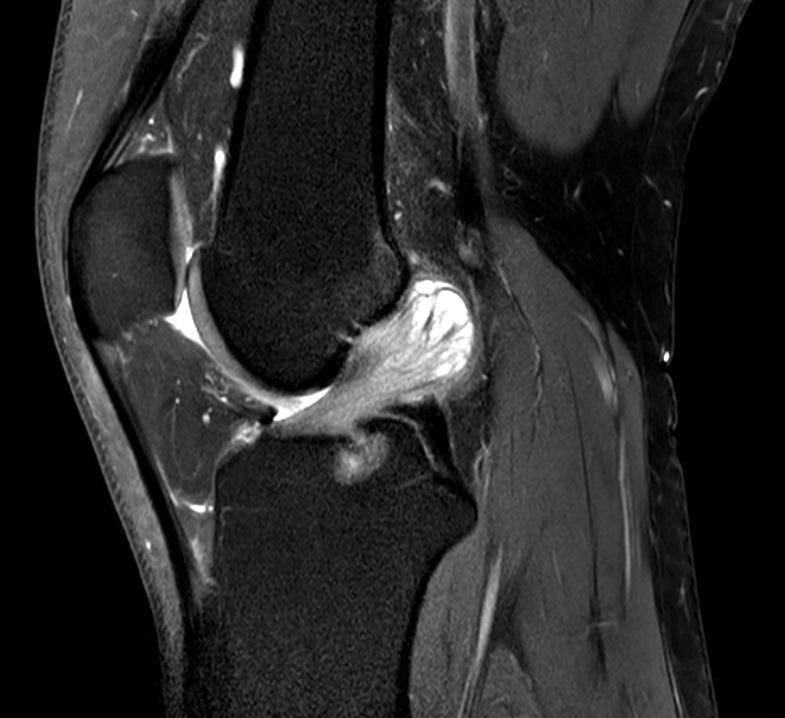

MRI van de linker knie

Een 39-jarige man komt bij de orthopeed vanwege een pijnlijke linker knie. Zijn voorgeschiedenis vermeldt 2 maal een partiële laterale meniscectomie links. Bij onderzoek is de knie stabiel en heeft deze een flexiebeperking tot 100°. De MRI-scan toont een afwijking.